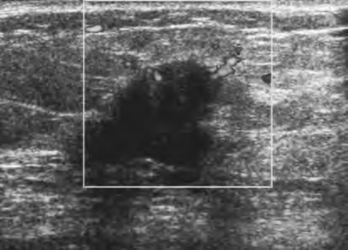

2.“中间型”乳腺癌声像图特点(图8-6) 某些细胞成分多、间质少的乳癌,如髓样癌,二维超声具有较多的良性特征,可表现为形态椭圆或类圆,内部回声不低,且较均质,后回声可增强,出现侧方声影。但是仔细分辨,该类型乳癌一般均无完整的包膜,部分肿瘤内部容易出现细密钙化,表现为“精盐征”。

图8-6 “中间型”乳腺癌二维声像图